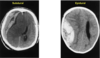

What are the MRI features of acute distemper virus?

- T2W hyperintense, T1W hypointense lesions in the cerebellum and brainstem with loss of gray–white matter distinction (areas of demyelination)

- Large, ill-defined lesions affecting the cerebral gray matter that are T2W and T2-FLAIR hyperin- tense and T1W iso- or hypointense; the may be attributed to the acute, post-ictal brain edema.

What are the MRI features of chronic distemper virus?

- Bilaterally symmetric hyperintense T2W lesions of the white matter just deep to the gray–white matter junction of the parietal and frontal lobes.

- T2W hyperintensity of the arbor vitae of the cerebellum causing loss of cerebellar gray–white matter junction.

- Ill-defined hyperintense T2W lesion of the caudal brainstem.

- Pachymeningeal contrast enhancement.